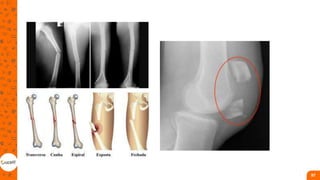

Classificação

Quanto ao traço

• incompletas a continuidade

óssea não é alterada, mas

apresenta uma rachadura que é

visível no exame de raios X;

• Essa rachadura pode se

apresentar de forma oblíqua,

espiral ou transversa.

• completas apresentam

especificamente uma perda da

continuidade óssea, gerando

substâncias residuais (pedaços de

ossos) que podem provocar danos

internos nos tecidos adjacentes.

Quanto ao tipo de força causador do trauma

• Força direita, indireta e de

torção

Fratura de diáfise da tíbia

• Ocorrem na maior parte dos casos, devido a

traumas de alta energia, como acidentes de

trânsito, quedas de altura e esportes de

contato;

• Como a tíbia é um osso com pouca

cobertura muscular, a maioria das suas

fraturas – fechadas e expostas – está

associada à lesão da pele e do tecido

subcutâneo.